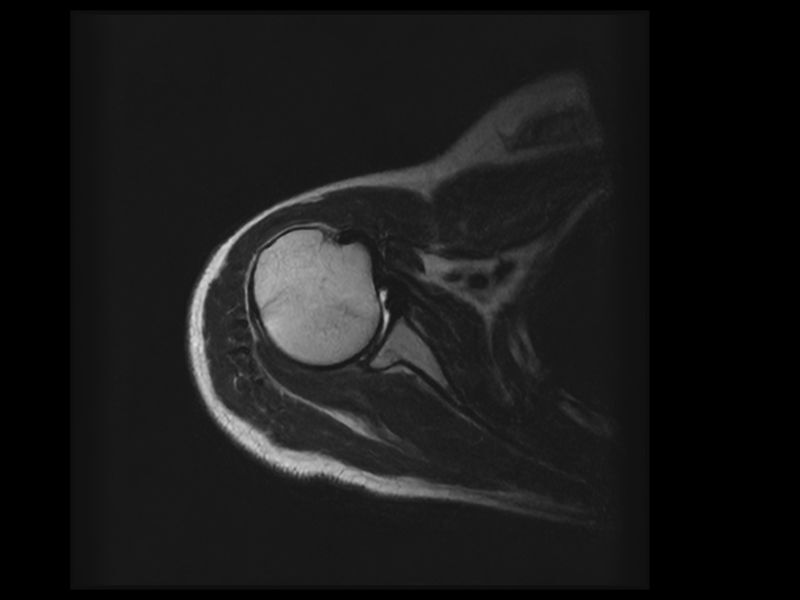

Clinical Images